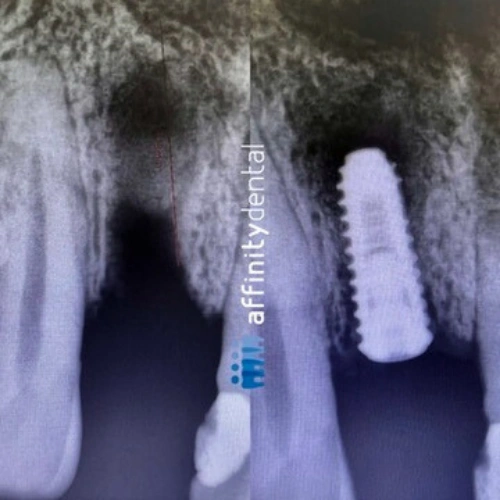

We begin with a comprehensive clinical evaluation and 3D imaging using Cone Beam CT and intraoral scanners. This helps us assess bone quality, design your custom surgical guide, and simulate the entire procedure in advance.

Implants are precisely placed based on the digital treatment plan. If the bone is sufficient and implant stability is achieved, we proceed with immediate restoration.